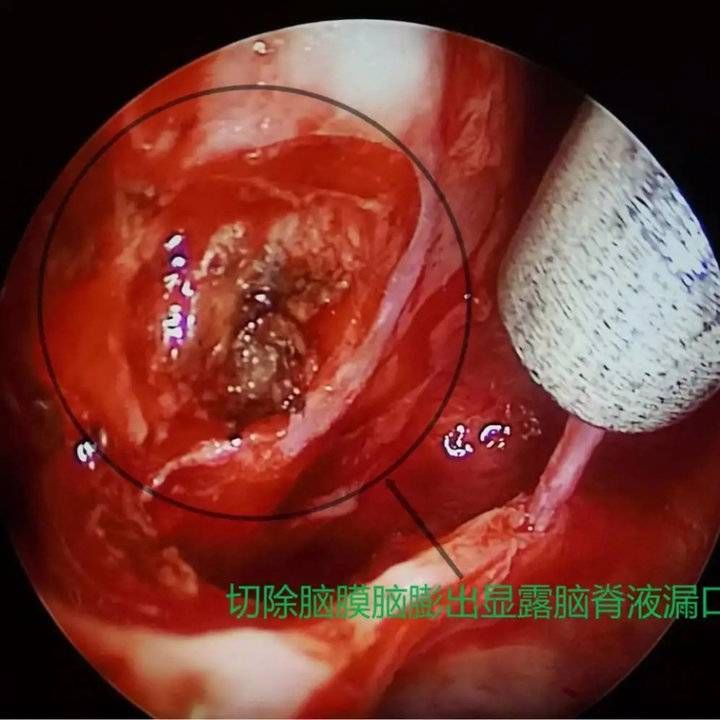

经呼吸科、麻醉科、耳鼻喉科及重症医学科评估后,8月4日,赵秋良主任团队为患者进行了鼻内镜下脑膜脑膨出切除+脑脊液修补+颅底重建手术。赵秋良主任介绍,这是全市首例鼻内镜下脑脊液修补手术,是鼻科鼻内镜微创手术里难度系数最高的四级手术之一,该手术充分利用人体自然腔道,全程在高清屏幕直视下完成,创伤小、愈后良好,术后并发症少,脑脊液修复的成功率高达90%。